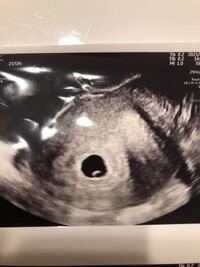

6週2日 心拍確認できた

妊娠6週3日 6w3d の超音波 エコー 写真

妊娠6週2日 6w2d の超音波 エコー 写真